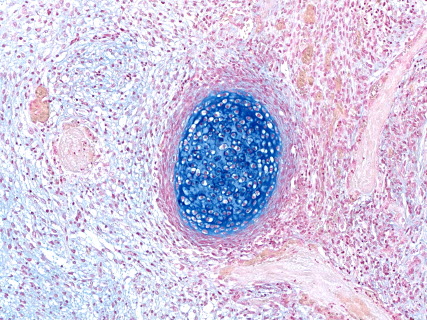

Anti-HLA staining (immunostaining) (xenograft)

Anti-human CD3 staining (immunostaining) (humanized-NOG mice)